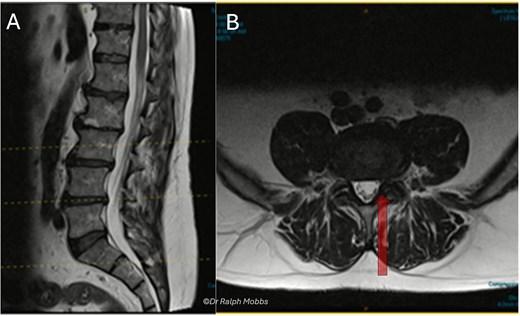

A 60-year-old female presented with a 3-year history of chronic left-sided S1 radiculopathy. MRI demonstrated stenosis of the left lateral recess at L5–S1, with no imaging indication of an underlying nerve root anomaly (Fig. 4).

Case 2 mid-sagittal (A) and axial (B) T2-weighted MRI at L5/S1 with lateral recess stenosis (arrow).